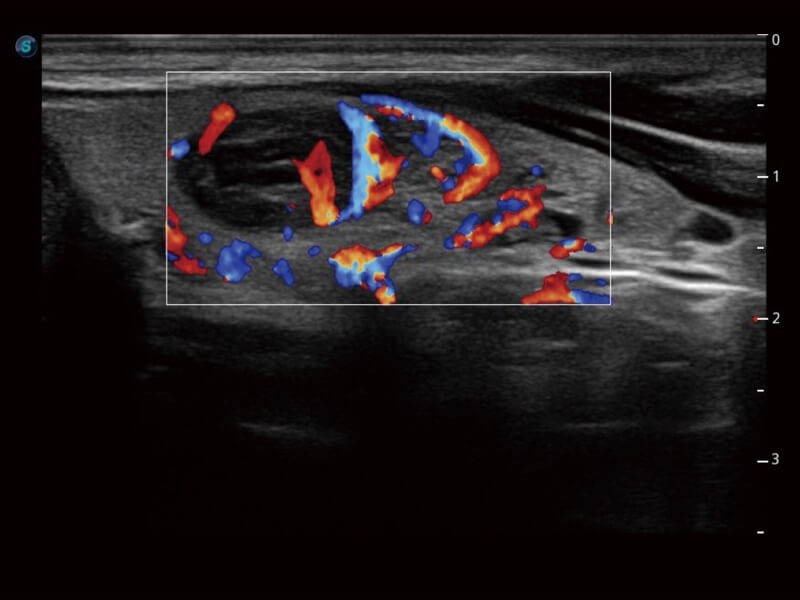

Die Bildqualität liegt immer im Zentrum definierter klinischer Ergebnisse. ELITE liefert eine leistungsstarke und klare Bildgebung, die durch eine leistungsstarke Architektur, hochmoderne Sonden und ausgeklügelte Verarbeitungsalgorithmen erzeugt wird, für ein höheres Maß an Klarheit und Vertrauen.

Mit Auto IMT wird die Messung der Dicke der vorderen und hinteren Intima-Media viel einfacher durch einfaches Platzieren des ROI.

Ultraschall wird immer vielseitiger und übernimmt immer mehr klinische Aufgaben. Als Vorreiter, der Ärzten dabei hilft, mehr zu erreichen, ist ELITE mit einer umfassenden Palette fortschrittlicher Funktionen für die Allgemeine Bildgebung, Gynäkologie/Geburtshilfe, Kardiologie und mehr integriert.

Ultraschall wird immer vielseitiger und übernimmt immer mehr klinische Aufgaben. Als Vorreiter hilft ELITE den Ärzten dabei, mehr zu erreichen, indem es mit einer umfassenden Palette fortschrittlicher Funktionen ausgestattet ist, die die allgemeine Bildgebung, die Geburtshilfe/Gynäkologie, die Kardiologie und vieles mehr abdecken.